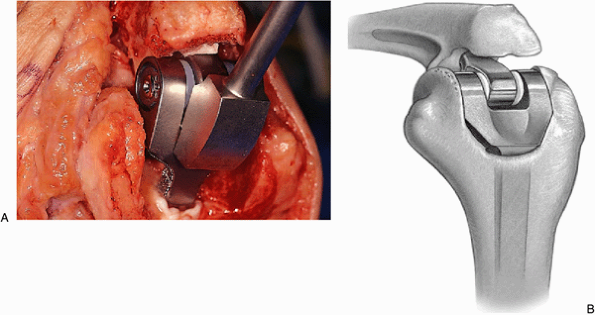

placed bone graft engages the flange at the time of implant coupling (Fig. 18-31).

The ulnar component is then articulated by placing a pin across the

humerus through the ulna and is secured with the “pin-in-pin” axis

system (Fig. 18-32).

![]() |

|

Figure 18-31. A,B:

After the ulnar component has been rigidly fixed, the bone graft is partially elevated and the humeral component is inserted to the point where the graft is captured by the flange, and this allows the juxtaposition and articulation of the ulna with the humeral component. |

Figure 18-32. The pin-within-the-pin articulating mechanism couples the device.